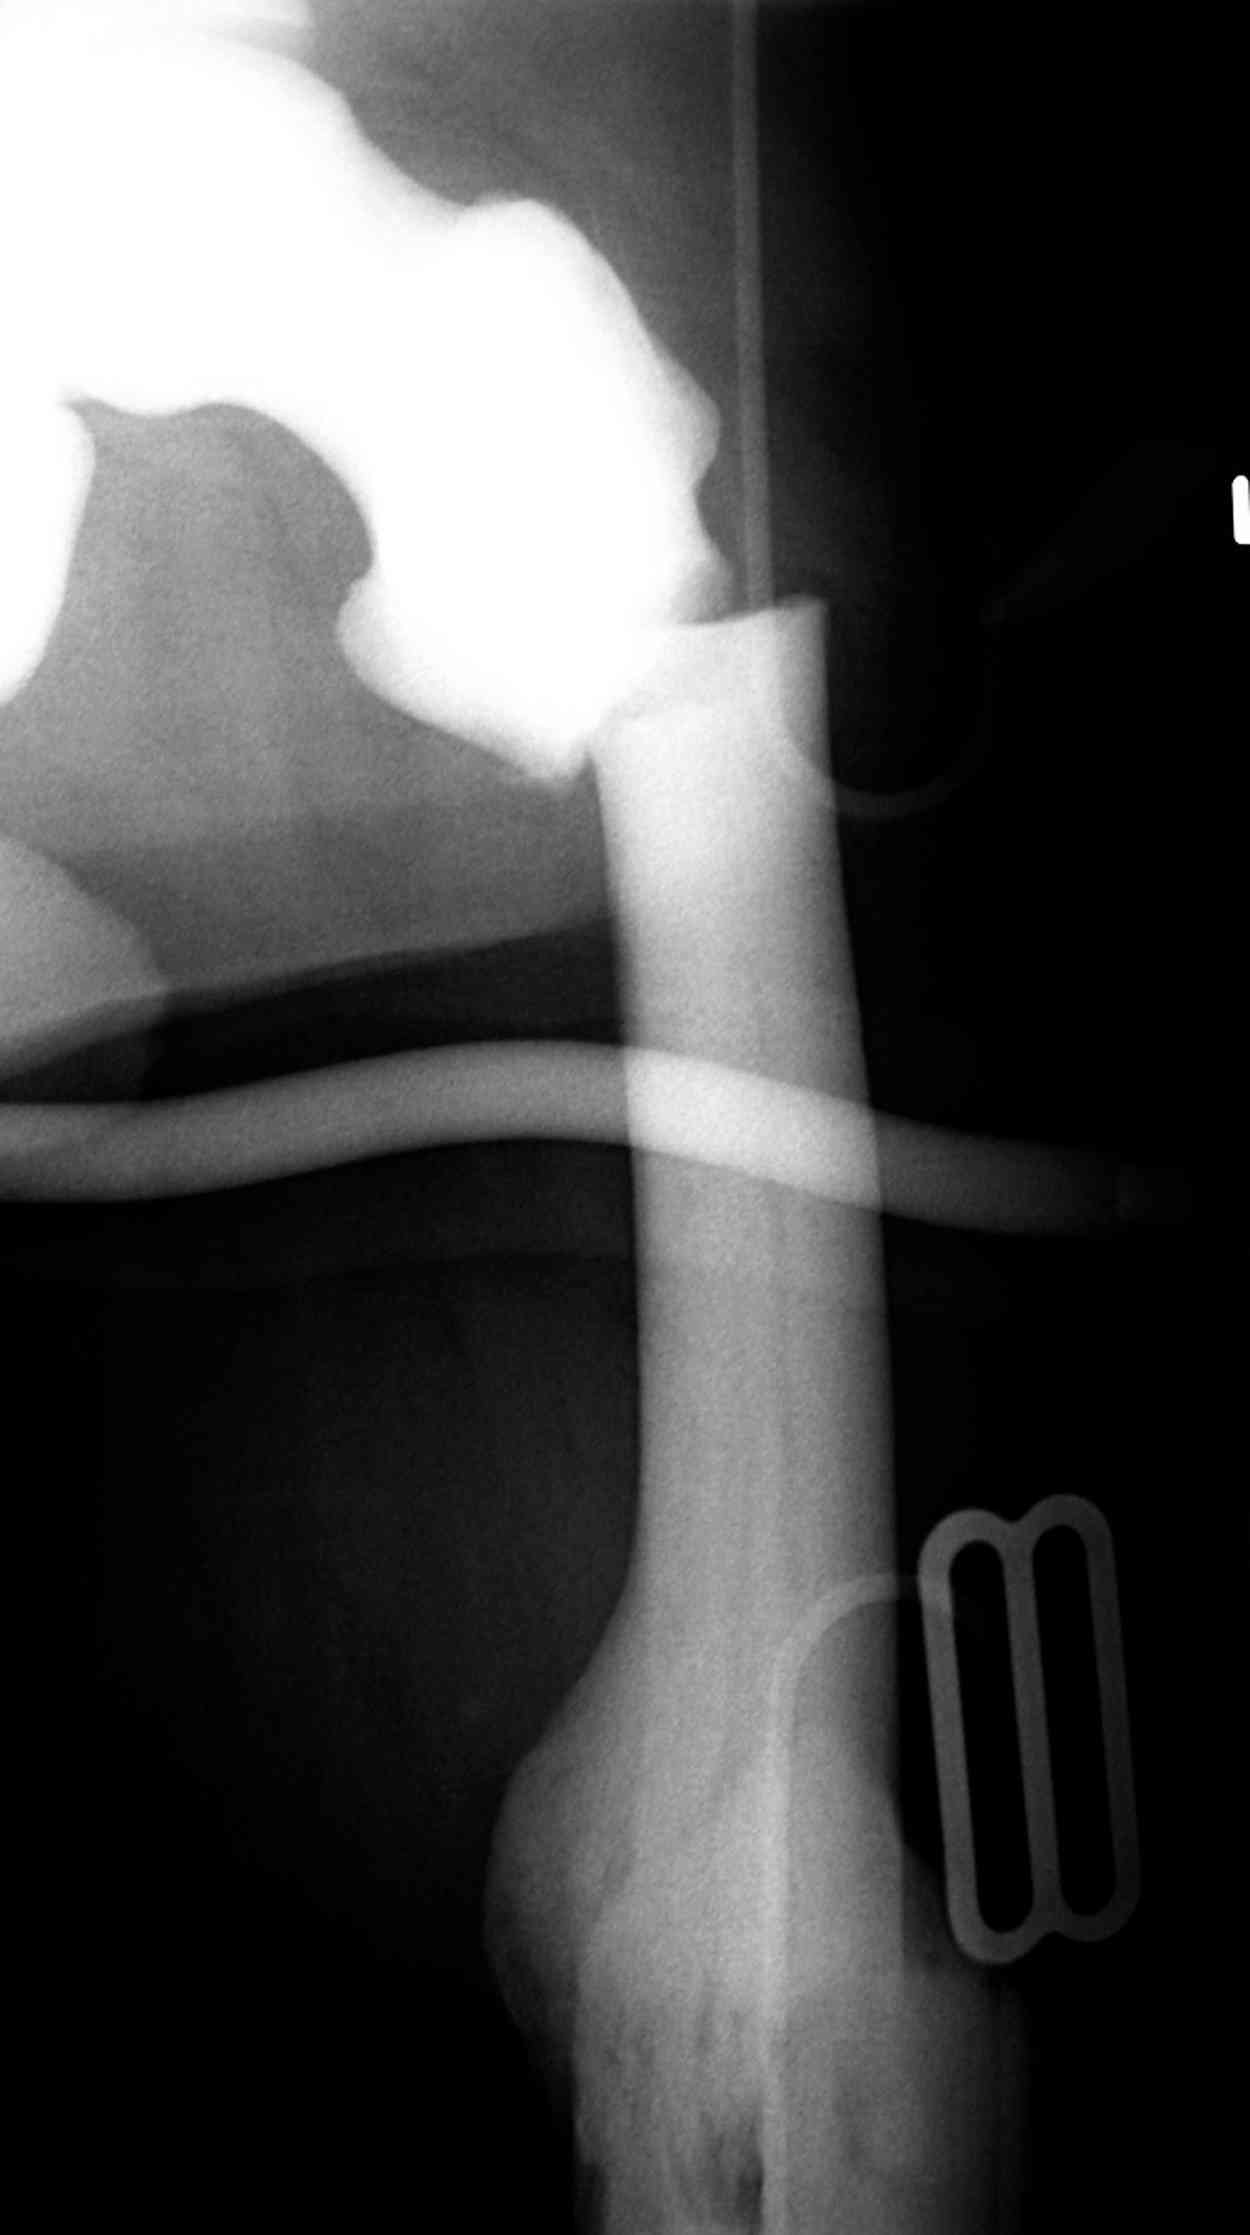

Здесь у меня дополнительные снимки с большим разрешением и в разных режимах, а то те дигитал снимки совсем очень блеклые, может, эти изображени изменят выбор тактики

После неудачной попытки скелетного вытяжения в первом мед.учреждении, после осмотра снимков и изучения истории, поставили диагноз “Остеопетроз” или мраморная болезнь, редкая наследственная костная паталогия, где имеется нарушение формации остеокластов.

Конечно, было бы идеальным применение интрамедуллярного остеосинтеза, но учитывая прежний собственный опыт (лечил перелом бедра) и

публикации, предупреждающие о трудностях при обработке кости (иногда из-за неподготовленности инструментария результатом была неадекватная фиксация перелома, или перенос операции из-за фактора усталости оперирующего персонала), решили применить пластину (и в этом же случае был выбран Synthes plate, так что представитель за два дня

зароботал... на десерт тоже).

Заказаны были дополнительные различные дрели, и на следующий день, усиленной бригадой, больного прооперировали, потратив на каждое отверстие около 25-35 минут, хотя сверлили с охлаждением по нарастающей по диаметру сверл и с их заменой каждые 2 мм сверления.

Теперь стоит задача со сращением перелома, из-за отсутствия литературных данных по применению костных стимуляторов при остеопетрозе, и не зная как поведет в этой среде Grafton, все таки надеюсь, что даст толчок к стимуляцию, решил применить пастообразную деминерализованную костную матрицу, расположив спереди между отломками.